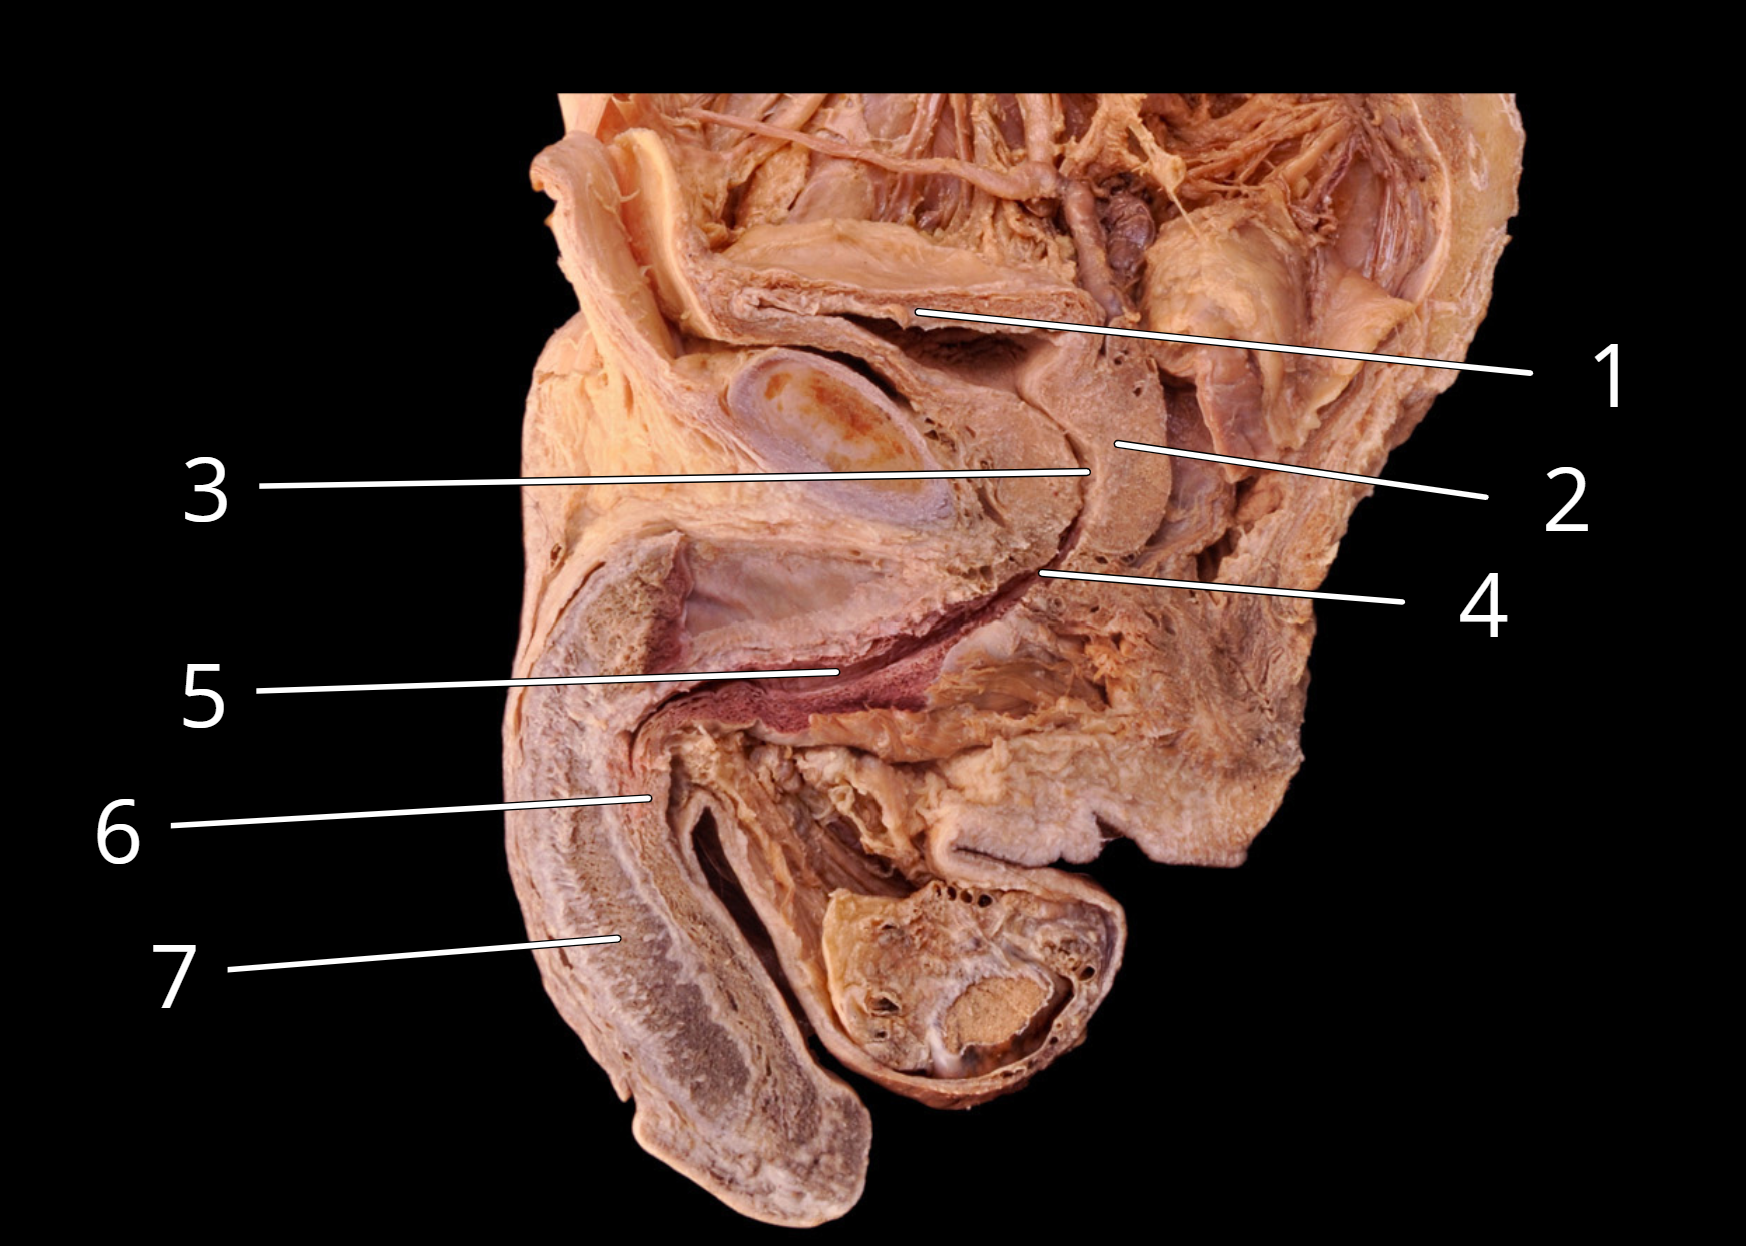

Male reproductive structures, sagittal view

1. Urinary bladder

2. Prostate

3. Prostatic urethra

4. Intermediate part of urethra (Membranous urethra)

5. Spongy urethra

6. Corpus spongiosum

7. Corpus cavernosum